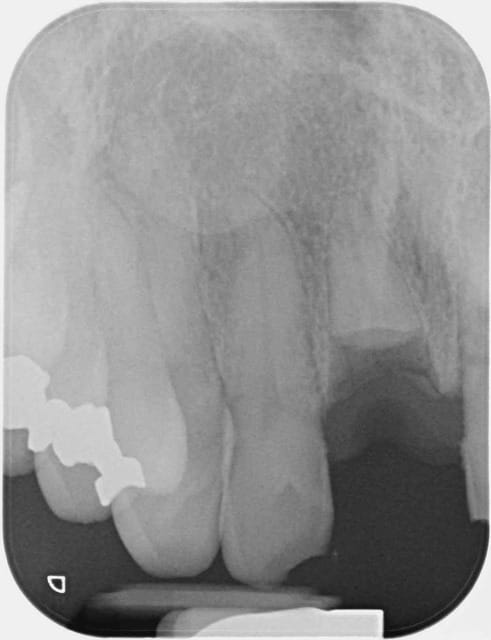

Ne jamais provoquer quelqu'un qui tient un marteau dans sa main !

Putain j'ai mal pour lui juste en regardant la photo.